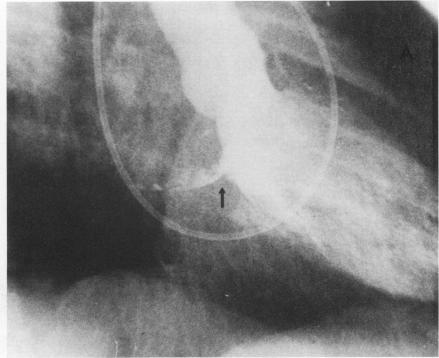

In two patients with atypical myxomas of the left atrium, two-dimensional echocardiography furnished valuable diagnostic information. In one patient, who had previously developed an embolism at the right brachial artery, M-mode echocardiography revealed an abnormal band of echoes within the left atrium. Two-dimensional echocardiography showed a globular cluster of echoes that remained within the left atrial cavity throughout the cardiac cycle; left ventricular angiography confirmed the ultrasonic findings of an intraatrial mass. At surgery, a calcified, nonprolapsing myxoma was excised from the interatrial septum. The second patient had clinical as well as M-mode echographic features of mitral stenosis. Cardiac catheterization showed a significant gradient across the mitral valve, but the left ventriculogram was normal except for an unusual pattern of mitral regurgitation. Subsequent two-dimensional echocardiography revealed a mass of echoes that prolapsed through the mitral valve during diastole. At surgery, a left atrial myxoma was found attached to the posterior mitral annulus. Our experience indicates that two-dimensional ultrasound is superior to conventional echocardiography for detecting unusual cardiac masses.

在两名患有非典型左房黏液瘤的患者中,二维超声心动图提供了有价值的诊断信息。在一名先前右侧肱动脉发生栓塞的患者中,M型超声心动图显示左房内有一条异常回声带。二维超声心动图显示一个球形回声团,在整个心动周期内都位于左房腔内;左心室造影证实了心房内肿块的超声检查结果。手术中,从房间隔切除了一个钙化的、不脱垂的黏液瘤。第二名患者有二尖瓣狭窄的临床和M型超声心动图特征。心导管检查显示二尖瓣跨瓣压差明显,但除了二尖瓣反流的异常模式外,左心室造影正常。随后的二维超声心动图显示一个回声团在舒张期通过二尖瓣脱垂。手术中发现一个左房黏液瘤附着于二尖瓣后瓣环。我们的经验表明,二维超声在检测不寻常的心脏肿块方面优于传统超声心动图。